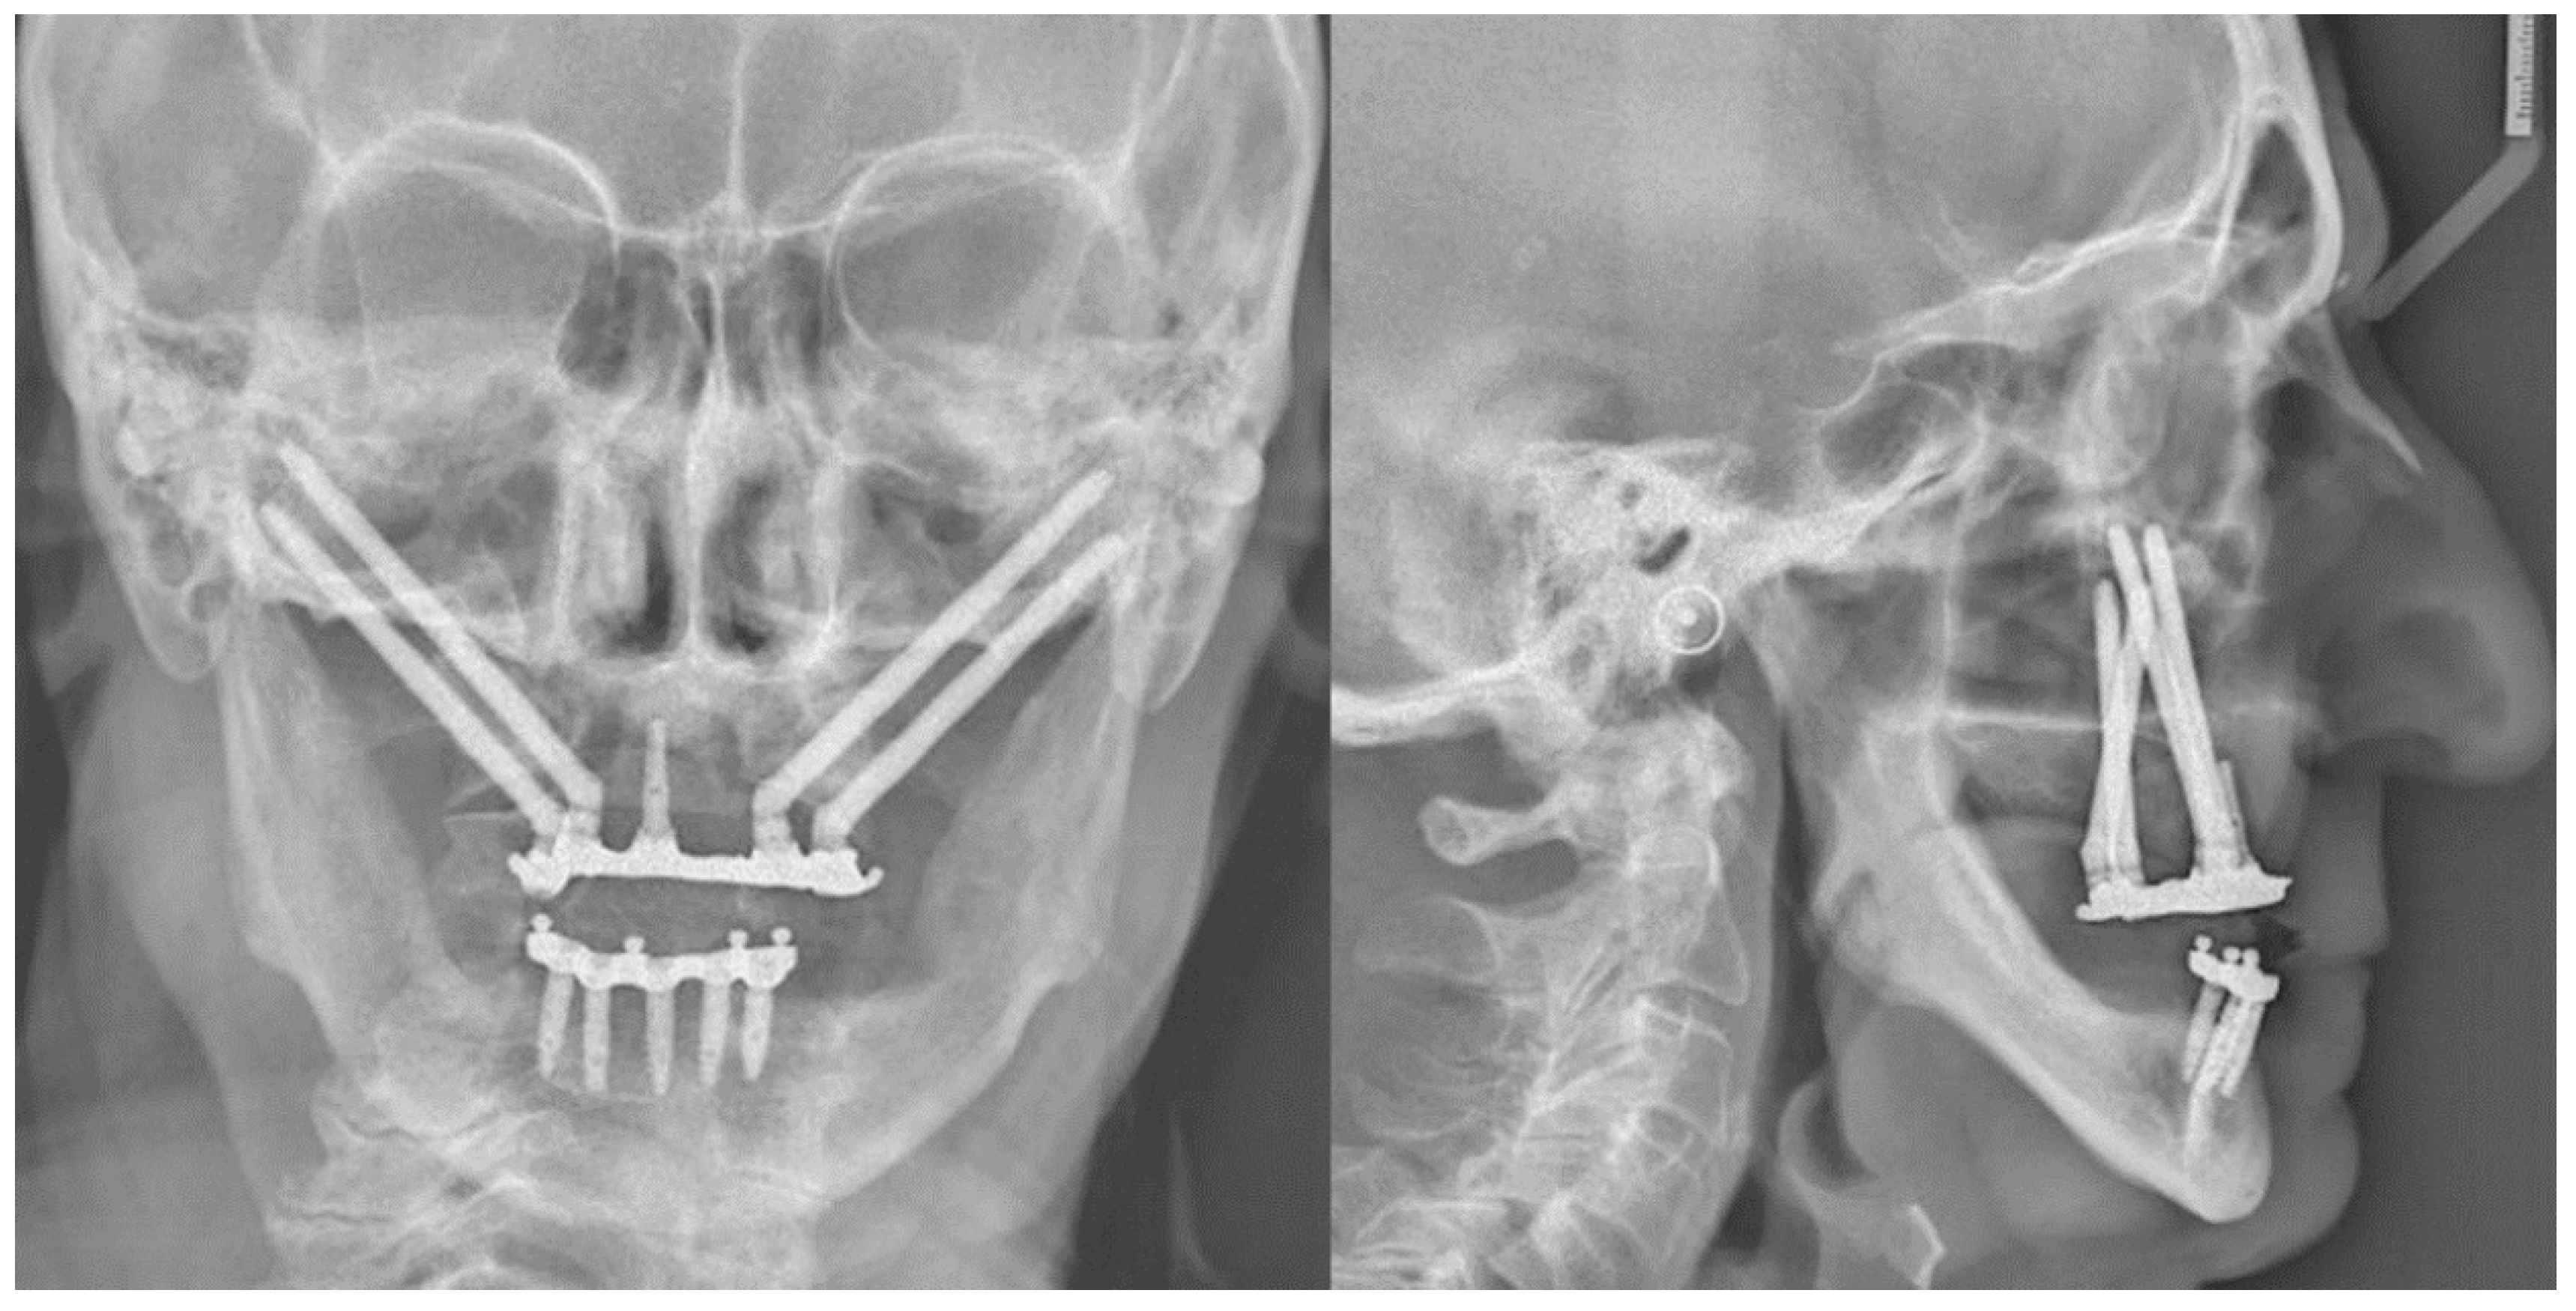

2. Case Report

3. Procedure